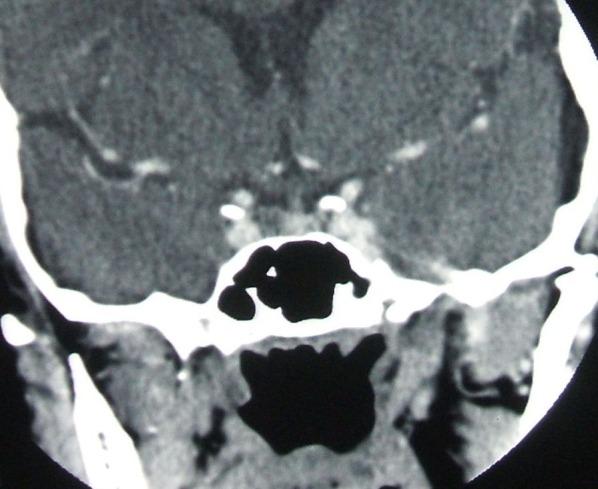

To observe the natural evolution of tumors' dimensions in a group of patients, diagnosed with nonfunctional pituitary microadenomas based upon hormonal measurements and computed tomography scan.

METHOD

There is a retrospective observational study on 149 patients hospitalized in our Clinic between 1994 and 2006. Initially, all the pituitary hormones and the computed tomography were performed. Only nonfunctional microadenomas were included (the maximum diameter 11 mm). 69 patients were examined for a long period of time--29.75 +/- 24.79 months by CT scan and secretory profile, repeated at different periods of time.

RESULTS

At the end of 29.75 months, the aspect of microadenoma was still present, without any statistically significant changes of the diameter. One of the cases became macroadenoma and another proved to be a microprolactinoma. Only 5 cases of all 149 presented a double lesion. No case of pituitary apoplexy was registered. These observations lead to the conclusion that it is not necessary to repeat the computed tomography scan sooner than 2 years once the diagnosis ofincidentaloma was established.

对1994年至2006年期间在我们诊所住院的149例患者进行回顾性观察研究。最初,进行了所有垂体激素检查和计算机断层扫描。仅纳入无功能微腺瘤(最大直径11毫米)。69例患者接受了长时间检查——通过CT扫描和分泌情况进行检查,在不同时间段重复进行,时间为29.75±24.79个月。

结果

在29.75个月结束时,微腺瘤的情况仍然存在,直径没有任何统计学上的显著变化。其中1例变为大腺瘤,另1例被证明是微泌乳素瘤。149例中只有5例出现双病变。未记录到垂体卒中病例。这些观察结果得出结论,一旦确诊偶发瘤,在2年内不必过早重复计算机断层扫描。